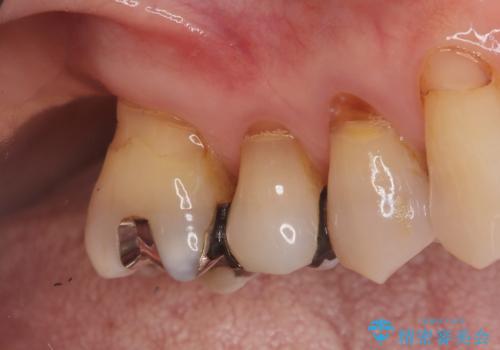

繰り返すプラスチックの欠けを解消。広範囲の修復に適したセラミッククラウン

欠けやすい大きなプラスチック充填から、耐久性の高いセラミッククラウンへ

銀歯からセラミックへ。右上奥歯の精密根管治療と審美修復